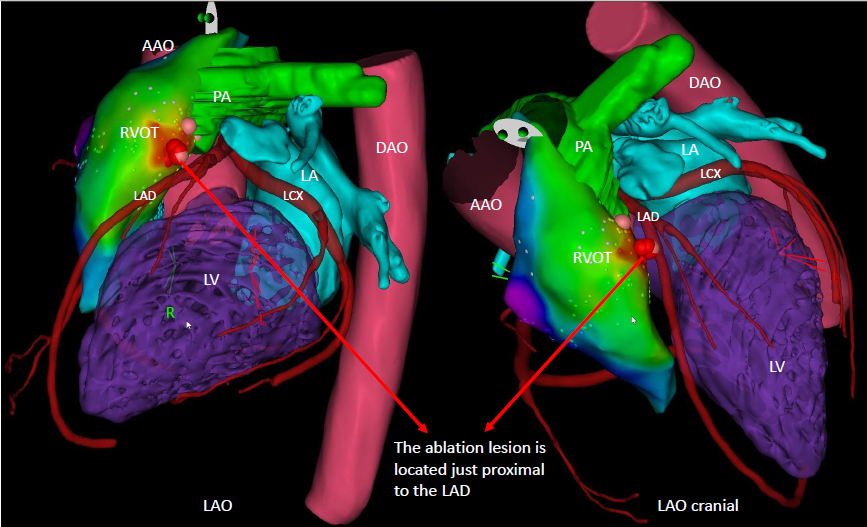

By integrating the MDCT coronary anatomy with the three-dimensional electroanatomical map and ablation lesion sites, it was demonstrated that the radiofrequency applications were directly adjacent to the proximal LAD, resulting in thermal injury and IMH formation.

This case underscores that LAD total occlusion can occur as a rare but serious complication of radiofrequency ablation at the anteroseptal RVOT, where the ablation site lies in close proximity to the proximal LAD. The underlying mechanism in this case was not atherosclerotic plaque rupture, but rather thermal injury leading to IMH formation. Importantly, prompt coronary intervention successfully restored coronary flow and preserved myocardial function.